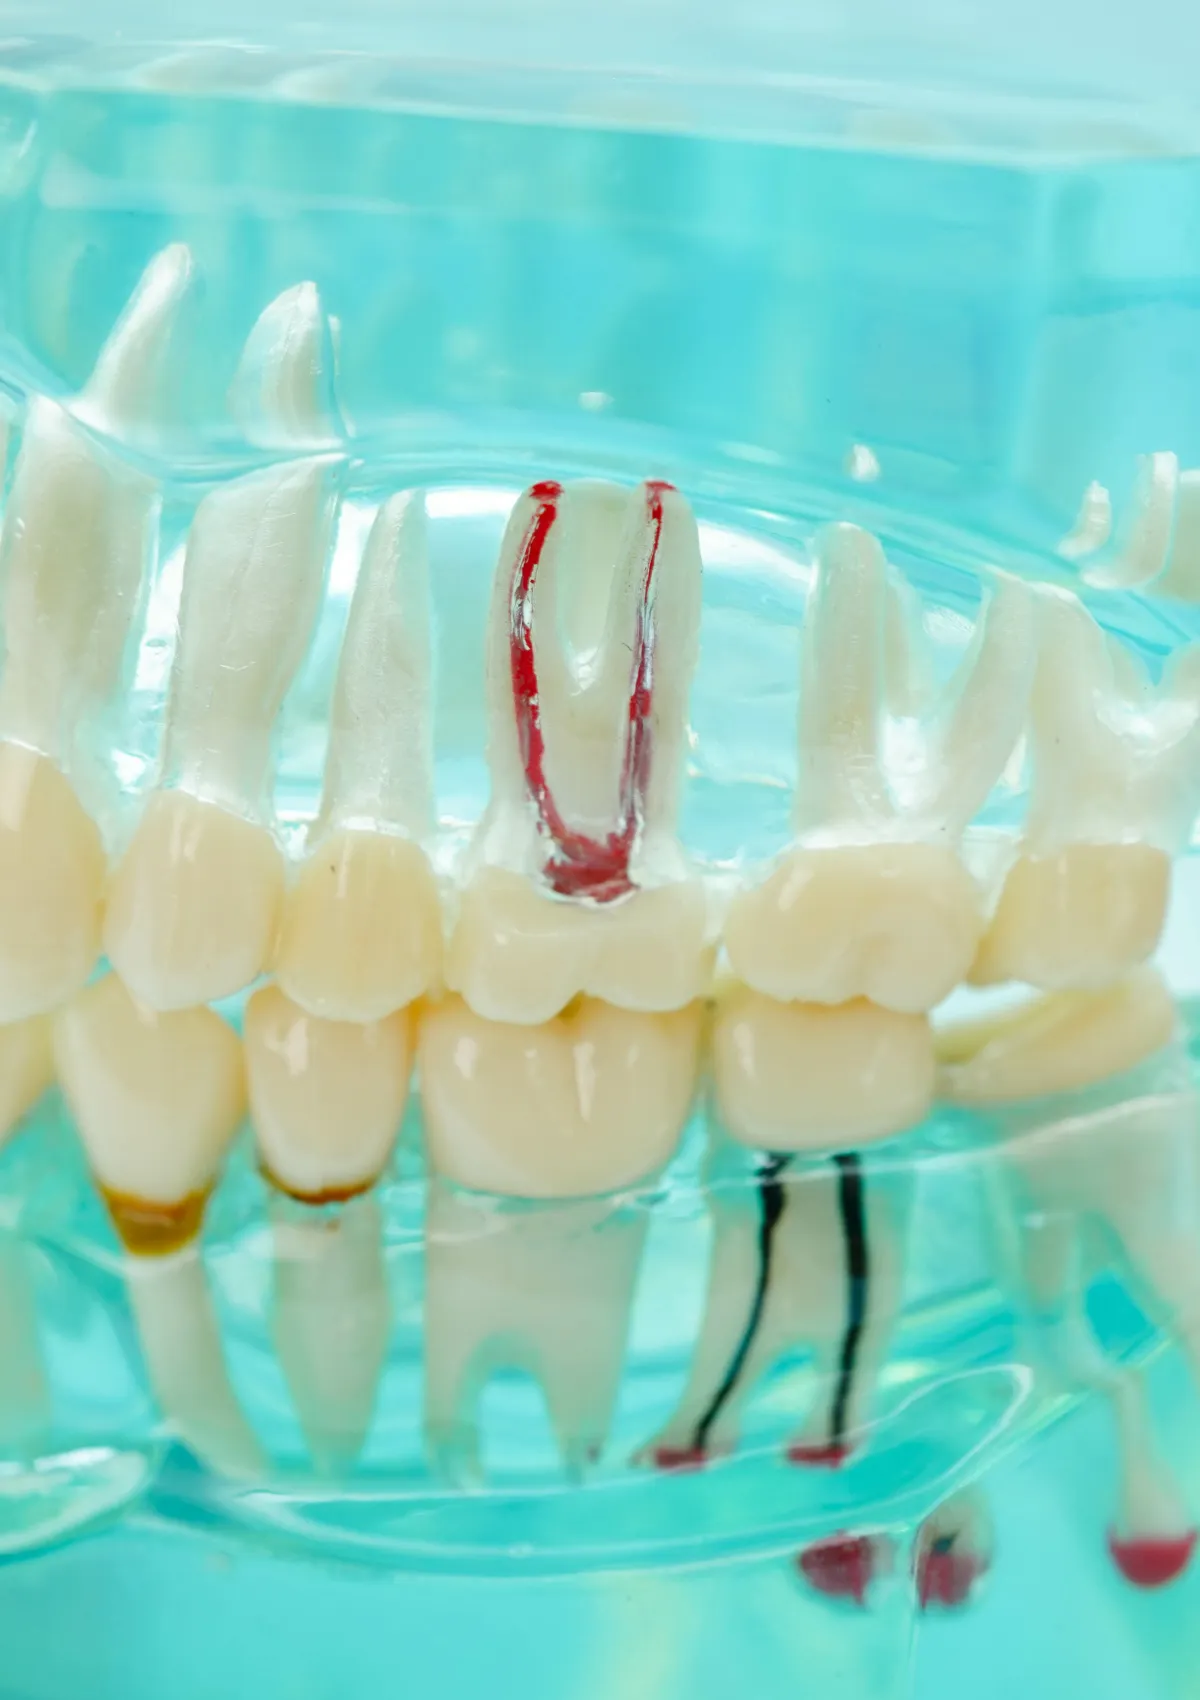

03根管治療とは、「歯の救命措置」

汚染された歯髄や細菌を徹底的に除去・消毒し、再び歯として機能させるための治療。それが「根管治療(歯内療法)」です。 しかし、複雑に入り組んだ根管内を肉眼だけで完璧に清掃することは不可能です。 だからこそ当院では、マイクロスコープやラバーダム防湿といった世界水準の設備を完備し、細菌を「見逃さない」「入れない」精密治療によって、かけがえのない天然歯を抜歯の危機から救い出します。

マイクロスコープ(歯科用顕微鏡)

肉眼の約20倍の視野で、ミクロン単位の汚れを除去します。手探りの勘に頼る治療から、見て治す治療へ。感染源の取り残しを極限まで防ぎます。

感染源の精密除去(Microscopic Debridement)

~ミクロン単位の汚染を見逃さない~

マイクロスコープの拡大視野下にて、細菌に侵された神経(歯髄)や血管、あるいは過去の治療で取り残された古い充填材などの感染物質を徹底的に除去します。肉眼では見えない微細な汚れまで除去することで、再発の最大の原因である「感染の取り残し」を極限まで防ぎます。